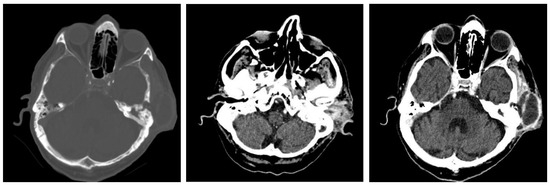

3.1.2. Computed Tomography and Magnetic Resonance Imaging

| CT Aspects | Number of Patients | Percentage |

|---|---|---|

| Fluid accumulation | 168 | 100% |

| Osteolysis | 152 | 90.47% |

| Osteocondensations | 128 | 76.19% |

| Cholesteatoma | 48 | 28.57% |

| Exocranial extensions | 48 | 28.57% |

| Intracranial extensions | 24 | 14.28% |

| Changes to the external auditory canal | 68 | 40.47% |

| Ossicular chain damage | 144 | 85.71% |